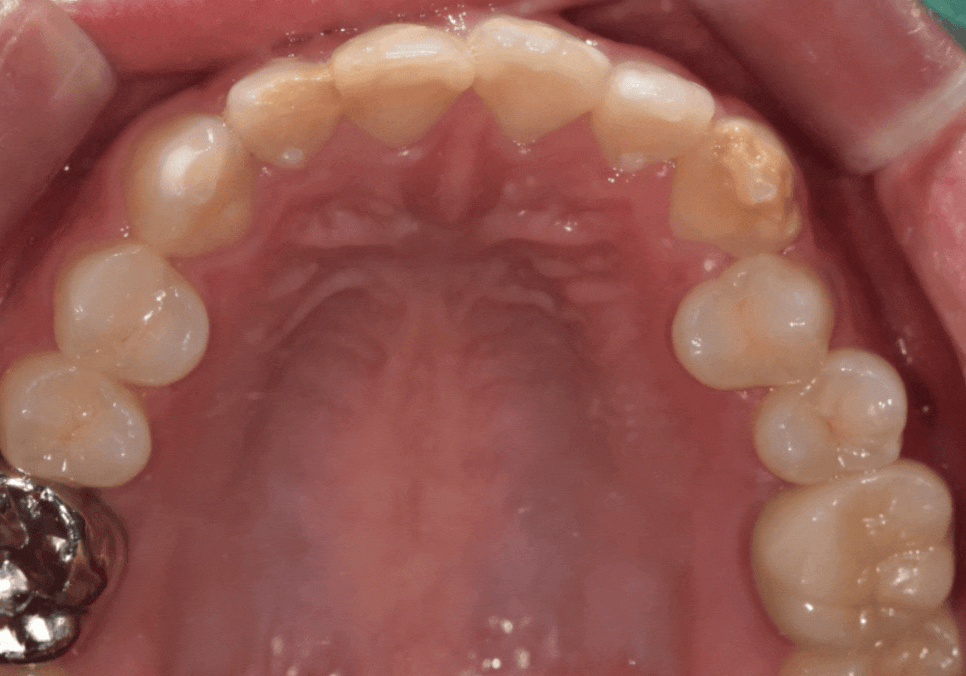

이번 환자분은 10대였고,

위 앞니 전반에 하얀 반점이

비교적 넓게 퍼져 있었습니다.

일부 치아는 반점이

치아 면적의 절반 이상을 차지해

앞니 톤이 균일하지 않은 상태였습니다.